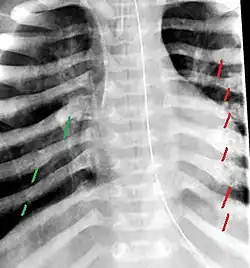

The material factual allegations of the amended complaint are as follows. Plaintiff was born on May 14, 1970. On repeated occasions during the first year of her life she was severely beaten by her mother and the latter's common law husband, one Reyes. On April 26, 1971, when the plaintiff was eleven months old, her mother took her to the San Jose Hospital for examination, diagnosis, and treatment. The attending physician was defendant Dr. Flood, acting on his own behalf and as agent of the defendant San Jose Hospital. At the time, the plaintiff was suffering from a comminuted spiral fracture of the right tibia and fibula, which gave the appearance of having been caused by a twisting force. Plaintiff's mother had no explanation for this injury. Plaintiff had bruises over her entire body. In addition, she had a non-depressed linear skull fracture which was then in the process of healing. Plaintiff demonstrated fear and apprehension when approached. Inasmuch as all plaintiff's injuries gave the appearance of having been intentionally inflicted by other persons, she exhibited the medical condition known as the battered child syndrome.

It is alleged that proper diagnosis of plaintiff's condition would have included taking X-rays of her entire skeletal structure, and that such procedure would have revealed the fracture of her skull. Defendants negligently failed to take such X-rays, and thereby negligently failed to diagnose her true condition. It is further alleged that proper medical treatment of plaintiff's battered child syndrome would have included reporting her injuries to local law enforcement authorities or juvenile probation department. Such a report would have resulted in an investigation by the concerned agencies, followed by a placement of plaintiff in protective custody until her safety was assured. Defendants negligently failed to make such report.

The complaint avers that as a proximate result of the foregoing negligence plaintiff was released from the San Jose Hospital without proper diagnosis and treatment of her battered child syndrome, and was returned to the custody of her mother and Reyes who resumed physically abusing her until she sustained traumatic blows to her right eye and back, puncture wounds over her left lower leg and across her back, severe bites on her face, and second and third degree burns on her left hand.

For example, the leading article by Kempe et al., op. cit., supra,[10] states that "A physician needs to have a high initial level of suspicion of the diagnosis of the battered-child syndrome in instances of subdural hematoma, multiple unexplained fractures at different stages of healing, failure to thrive, when soft tissue swelling or skin bruising are present, or in any other situation where the degree and type of injury is at variance with the history given regarding its occurrence . . . ." (Id., at p. 20.) Of the different types of fractures exhibited, an arm or leg fracture caused by a twisting force is particularly significant because "The extremities are the 'handles' for rough handling" of the child by adults. (Id., at p. 22.) The article also contains numerous recommendations to conduct a "radiologic examination of the entire skeleton" for the purpose of confirming the diagnosis, explaining that "To the informed physician, the bones tell a story the child is too young or too frightened to tell." (Id., at p. 18.) Finally, on the subject of management of the case it is repeatedly emphasized that the physician "should report possible willful trauma to the police department or any special children's protective service that operates in his community" (id., at p. 23) in order to forestall further injury to the child: "All too often, despite the apparent cooperativeness of the parents and their apparent desire to have the child with them, the child returns to his home only to be assaulted again and suffer permanent brain damage or death." (Id., at p. 24.)